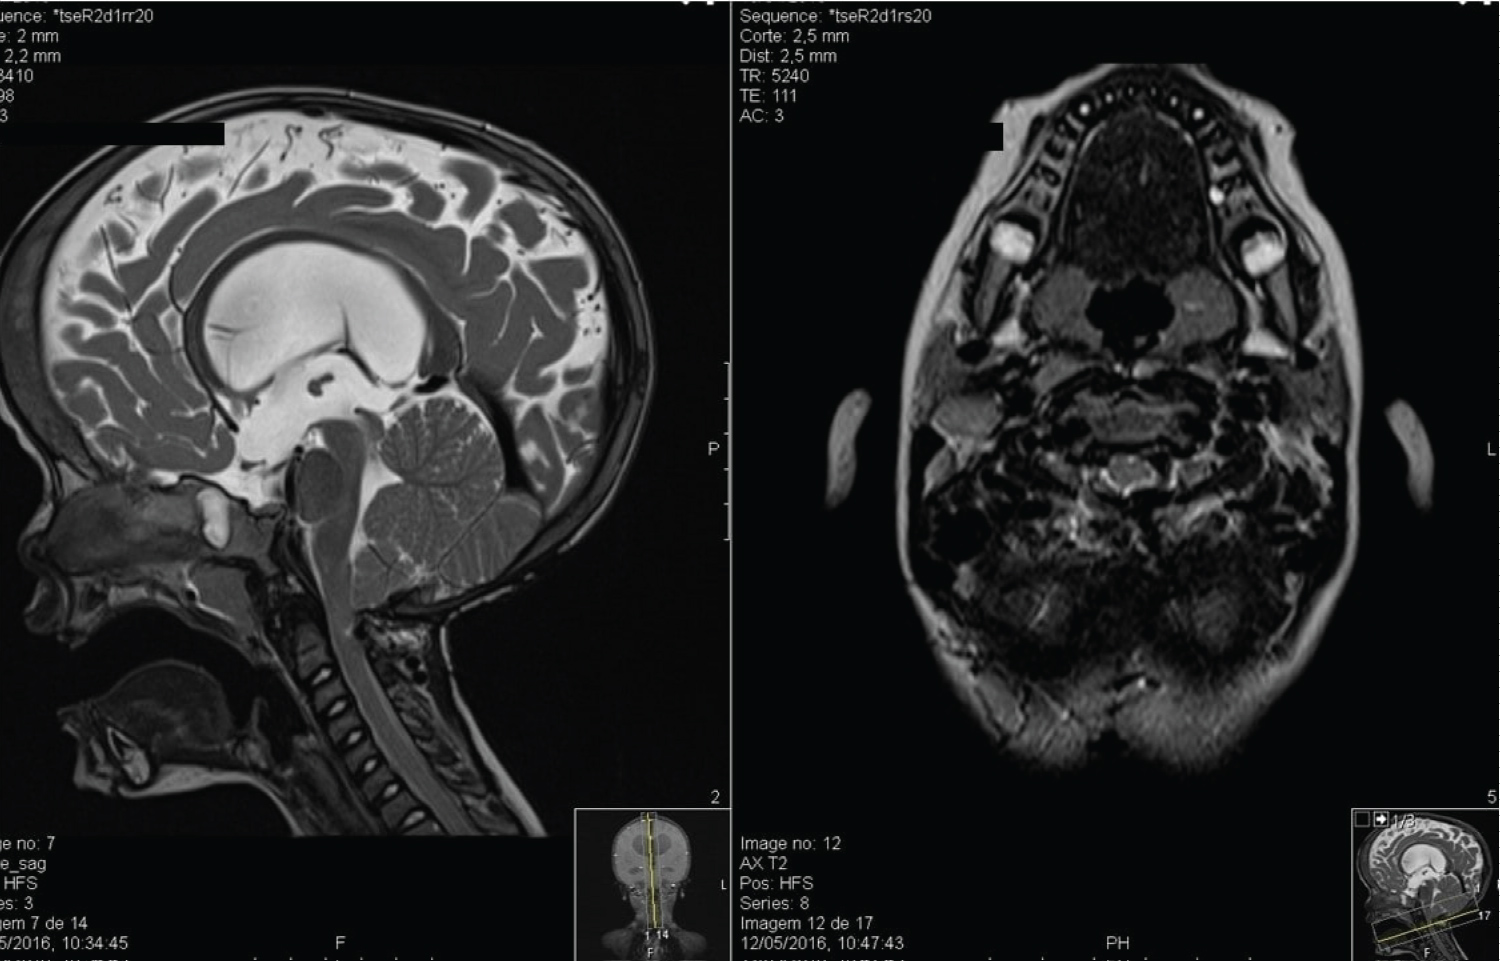

The patient was admitted in the paediatric Intensive Care Unit for two days after surgery. The postoperative period was uneventful. There were no respiratory complications and opisthotonos resolution was observed. A postoperative MRI showed a good cervicomedullary decompression (Figure 3). Good clinical outcome was observed during follow up. Seven years after surgery the child presents no neurological impairment (mRankin scale grade 1) nor any respiratory problems (Figure 4).

Figure 3: Postoperative MRI revealing a proper cervicomedullary decompression. View Figure 3

A caucasian male was born by caesarean dystocic delivery at 41 weeks after an uneventful pregnancy. There was no previous familiar history of skeletal dysplasia nor other hereditary diseases. He presented postpartum jaundice which was treated with phototherapy for four days. In addition, he had a patent ductus arteriosus without hemodynamic repercussion and did not require intervention. At five months, he presented poor cephalic control, a cephalic perimeter crossing percentile lines upwards, and increased tension on the anterior fontanelle. Growth parameters of weight and length were harmonious and within the normal range not suggesting dwarfism/AChP. He had up-slanting palpebral fissures, a short neck and narrow thorax. He also had clinodactyly of the fifth finger in both hands and bilateral metatarsus adductus. Moreover, vertebral bodies malformation from Th8 to Th12 due to ossification centre defect causing hemivertebrae in Th10 and Th11 and, consequently, a scoliotic curve, were visible on skeleton X-rays. No relevant changes were found on long bones. Endocrine system workup was normal. He was referred to medical genetics. To present date no pathogenic variants explaining the phenotype have been identified. Transfontanellar ultrasound imaging showed hydrocephalus. Brain MRI confirmed hydrocephalus with periventricular oedema due to an obstruction of the CSF outflow from the 4th ventricle. Additionally, malformation of the craniovertebral transition was observed, with a short clivus, a small posterior fossa with a narrow foramen magnum, and hypoplasia of the posterior atlas arch with marked cervicomedullary compression (Figure 5). An endoscopic third ventriculocisternostomy was successfully performed to treat hydrocephalus. The postoperative outcome was favourable with a stabilization of the cephalic perimeter and a normotensive anterior fontanelle. During follow up, however, at one year of age, the child presented new-onset difficulty in cephalic control with a tendency to postural hyperextension, and difficulty in manipulating and controlling objects.

Figure 5: Patient 2- Sagittal plane MRI showing compression in the cervicomedullary transition (T2-weighted sequence). View Figure 5